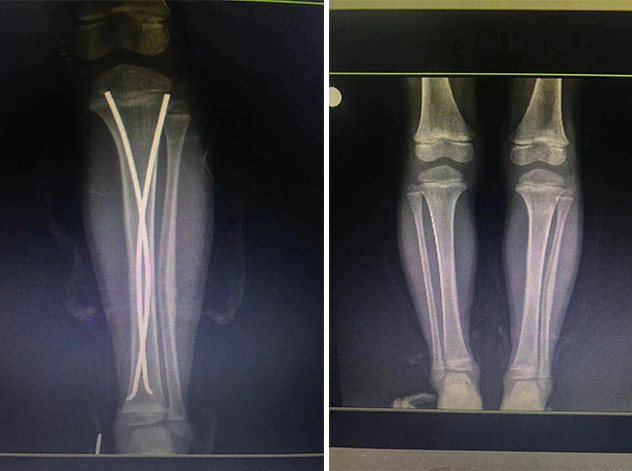

在接下來的康復(fù)過程中,睿睿非常配合,恢復(fù)的非常好。今年4月12日,睿睿拆除了左腿里的彈性釘。

拆前拆后對比